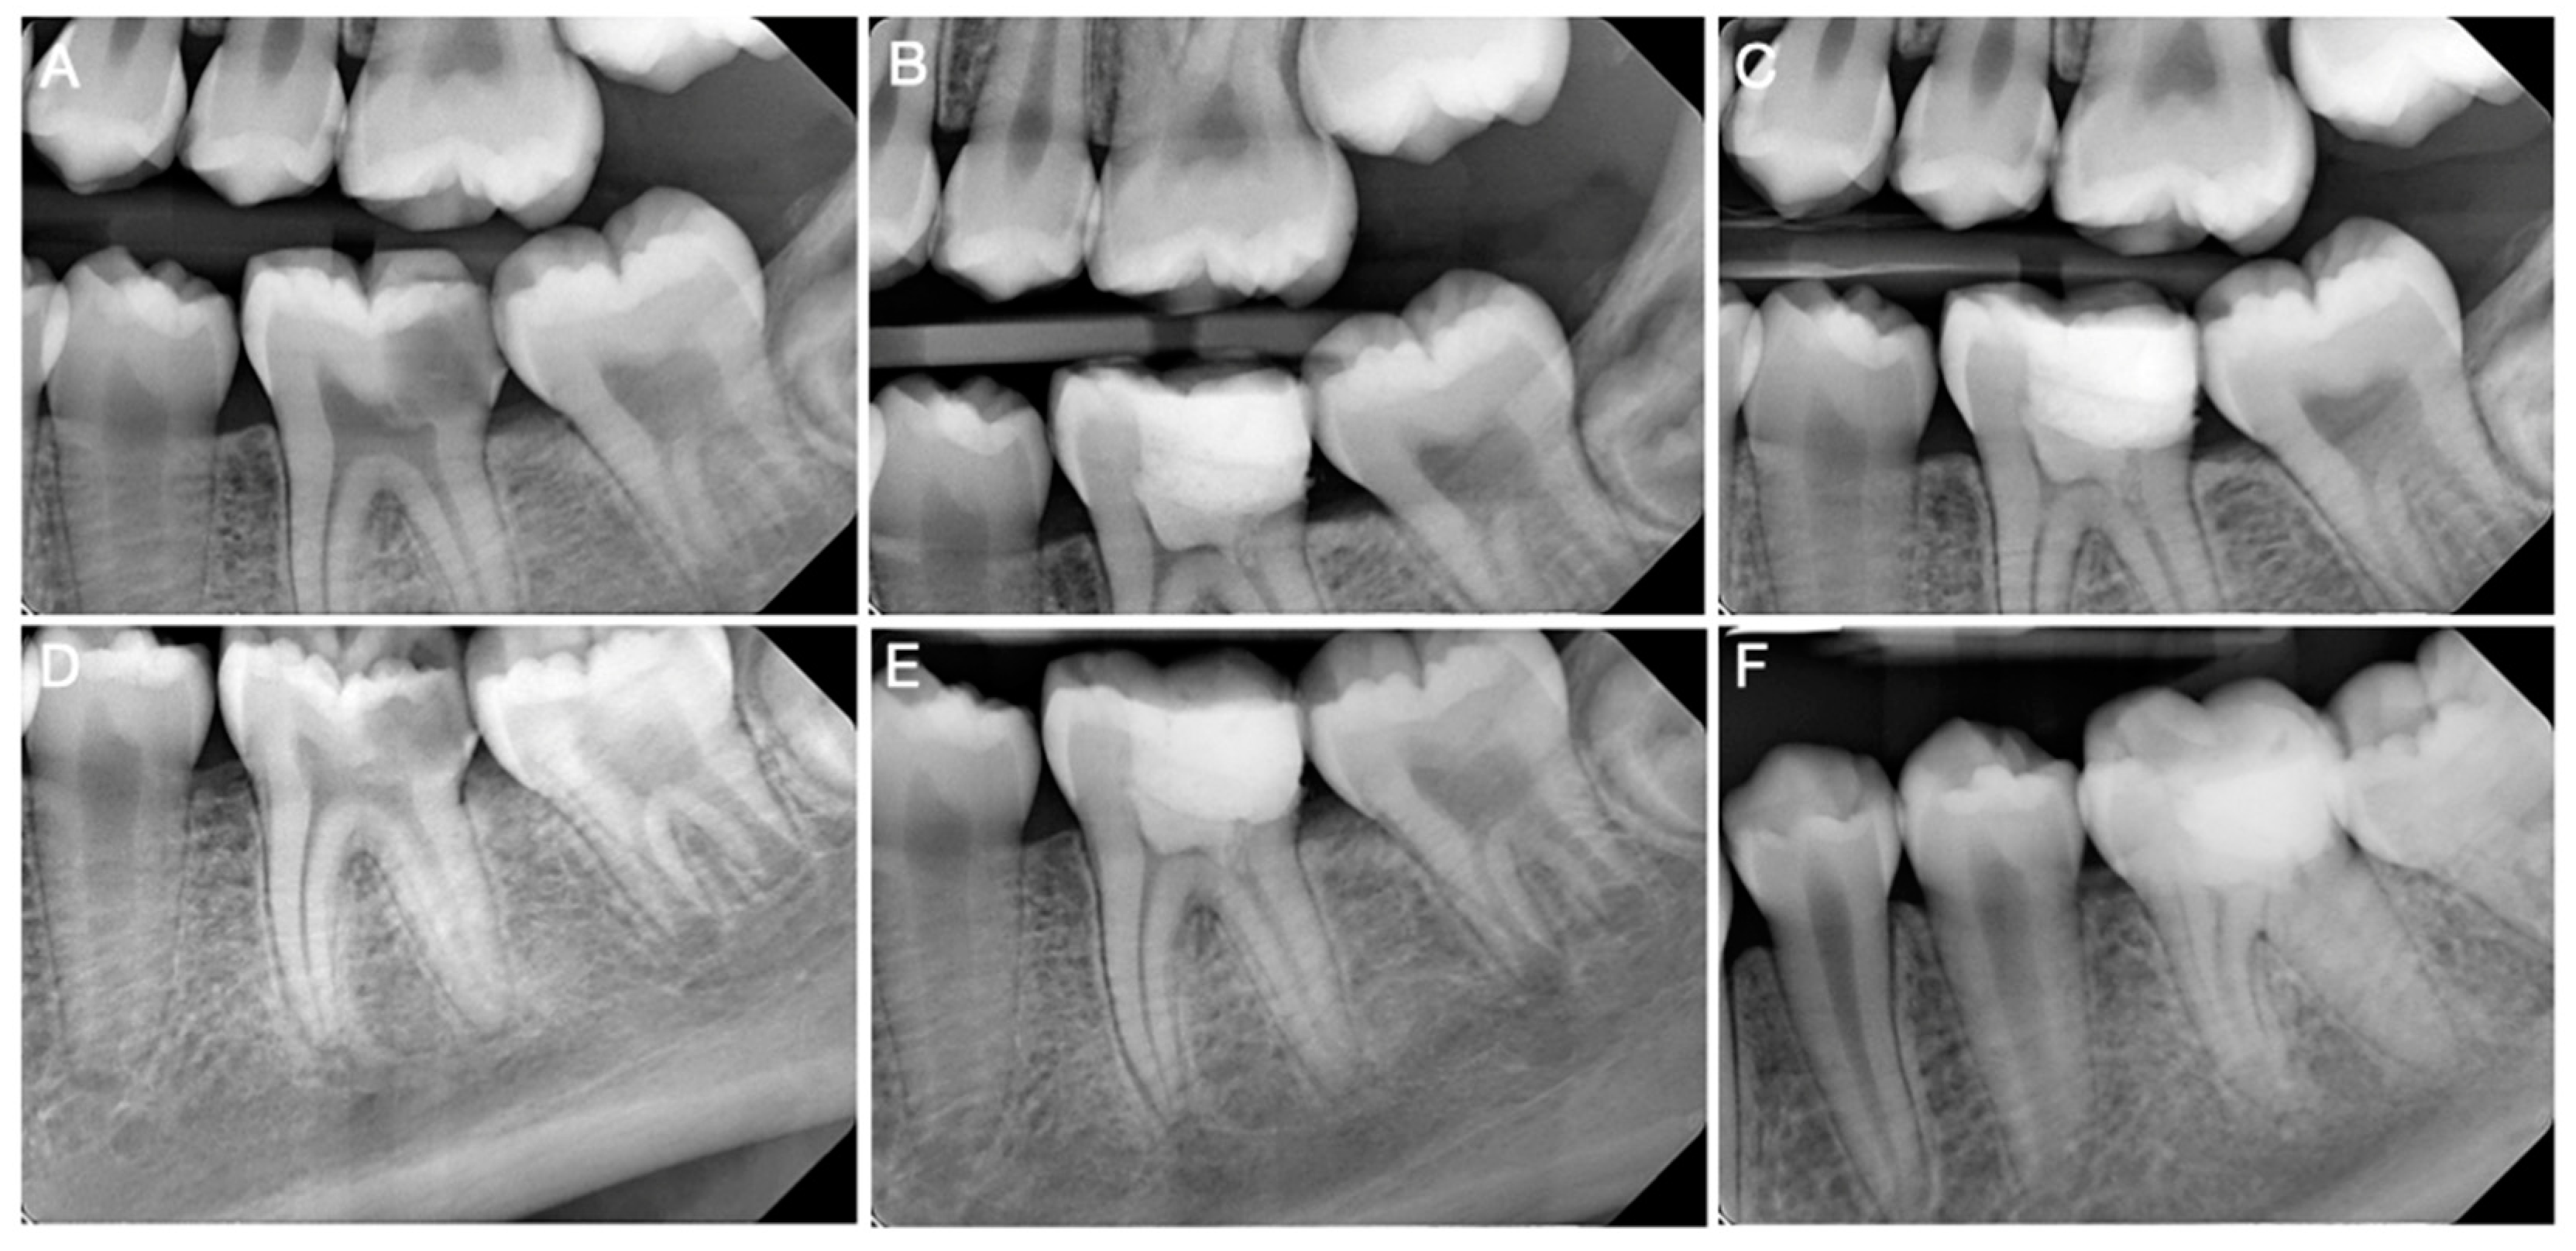

| Kim and Solomon, 2021 [66] | In vivo | Twenty-four roots from mature canine premolars were equally divided into three groups: blood clots (BC), collagen membranes (CM), and dHACMs.

| Fibrous connective tissue was present in all groups, most predominatly in the dHACM group. Odontoblast-like cells were found only in the dHACM group. Intracanal mineralized tissue was observed only in the BC and CM groups. More periapical inflammation was observed in the BC group than in the dHACM group. | dHACMs may be useful for cell homing-based pulp regeneration in mature teeth. |